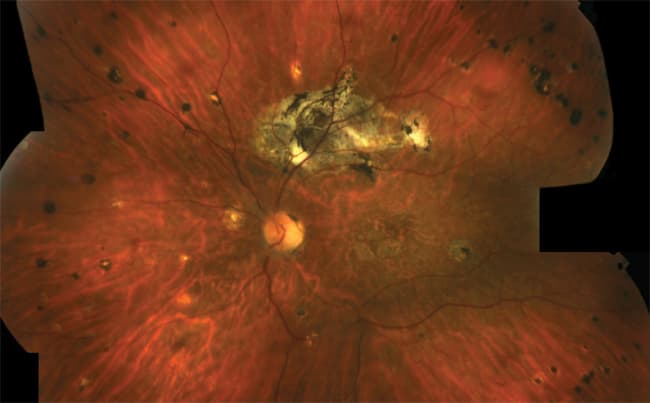

Figure 2. Composite image of the left eye, displaying similar features with respect to the right eye, but showing also an extensive area of fibrous metaplasia along the superotemporal arcade.

Visual acuity was 1/10 in both eyes, and the intraocular pressure was 14 mm Hg. Biomicroscopic fundus examination confirmed the diagnosis of FF. Indeed, several flecks at the level of the retinal pigment epithelium were detectable, whereas the macular region showed wide atrophic changes. In the left eye, along the course of the superotemporal vascular arcade, a wide fibrous metaplasia with placoid aspect and irregular pigmentation was evident. Interestingly, multiple punched-out spots were visible in the periphery of both eyes, assuming a linear streaks disposition (Figures 1 and 2).